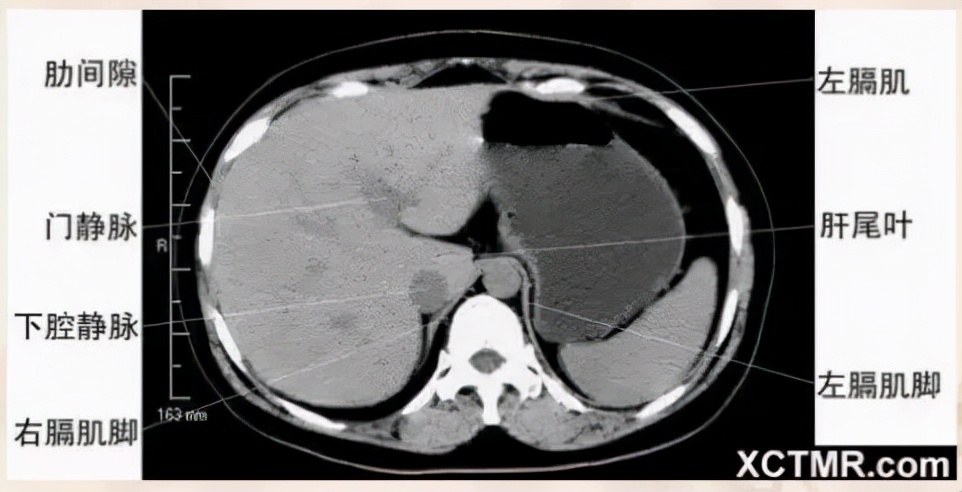

腹部CT